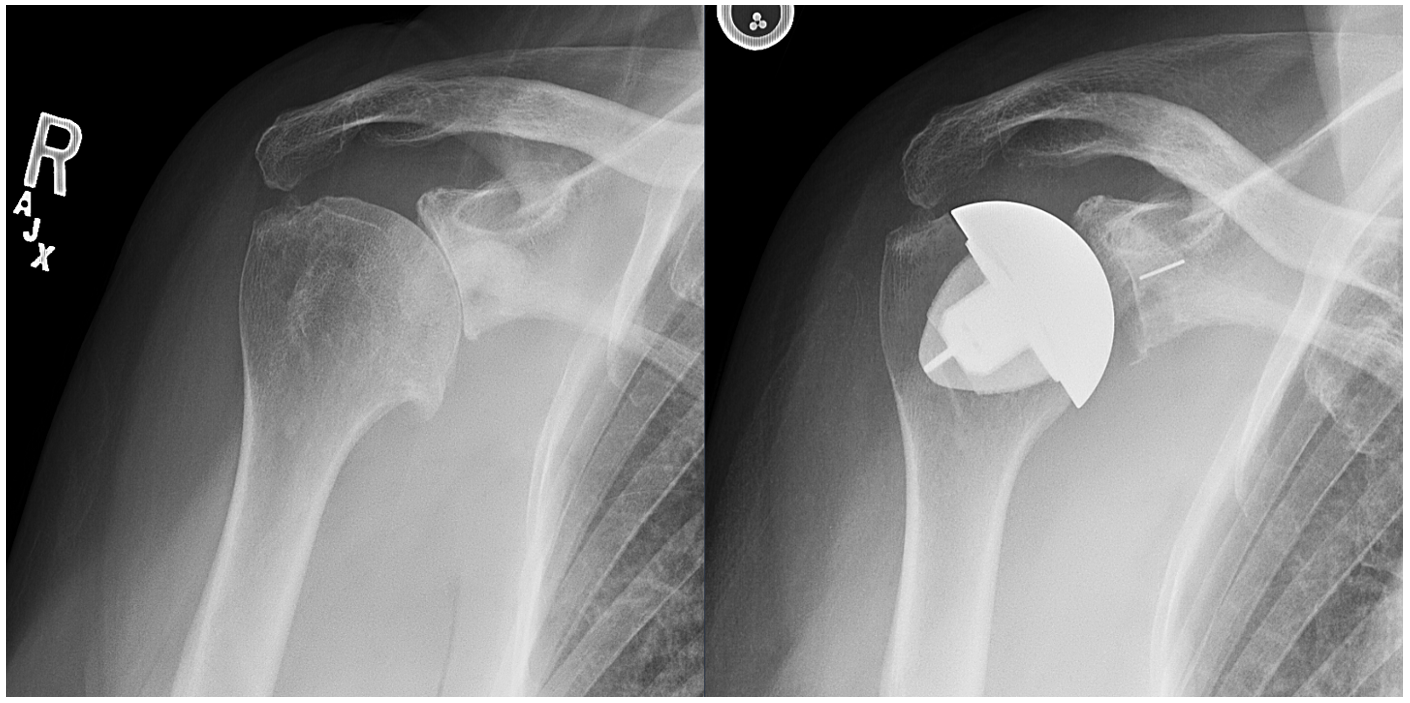

Clinical and radiologic following total shoulder arthroplasty

Clinical and radiologic following total shoulder arthroplasty What Is A Stemless Shoulder Replacement Shoulder replacement surgery is an operation to replace your damaged shoulder joint with an artificial joint. This technology has been around for many years. Anatomic total shoulder arthroplasty is the replacement of the humeral head and glenoid surfaces with the. 4.5/5 (36) Stemless shoulder arthroplasty is a minimally invasive procedure that repairs or replaces an injured shoulder. You can. What Is A Stemless Shoulder Replacement.